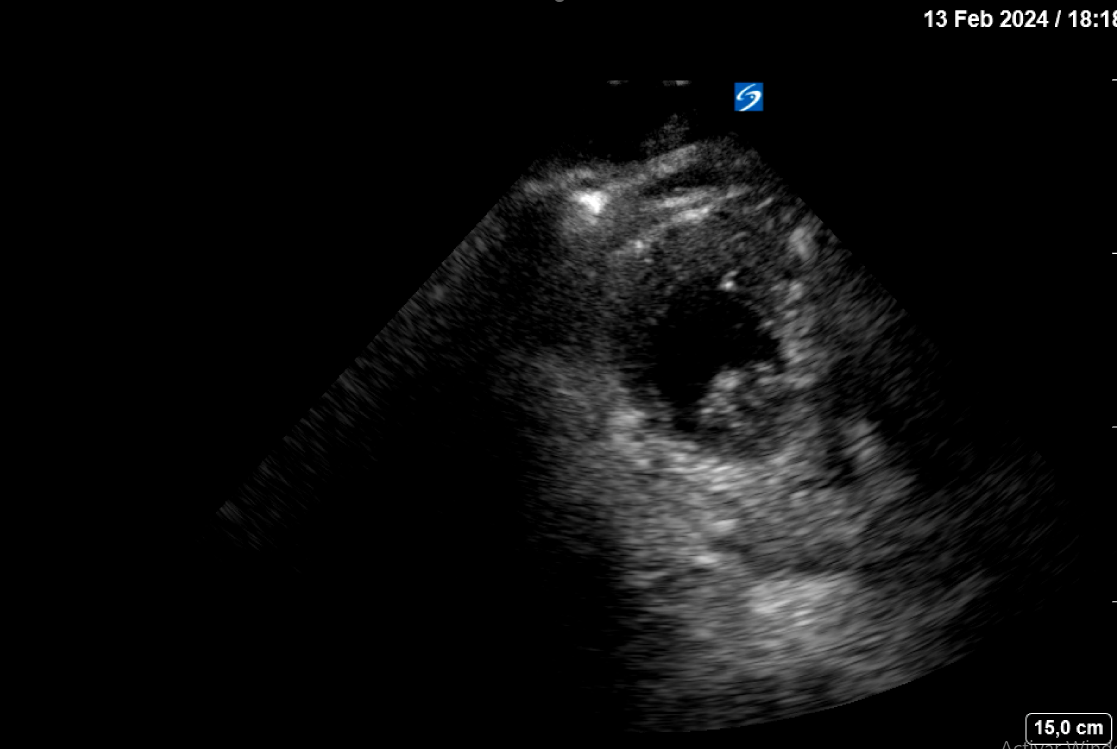

La estabilización hemodinámica junto a los parámetros clínico-ecográficos indican un taponamiento fibrinoso de la rotura cardíaca. Se decide ingreso en planta de medicina interna tras pico de troponina de 7000 pg/mL con el diagnóstico rotura cardíaca contenida. A las 10 horas de la 2ª ecografía clínica y antes de su traslado a una planta médica, se realiza una tercera ecografía clínica dirigida estando el paciente consciente, estable sin dolor. En el mismo se aprecia el mismo derrame pericárdico moderado idéntico al objetivado previamente, pero hay un nuevo hallazgo en el ápex del VI: un trombo intracavitario adherido (imagen 2).